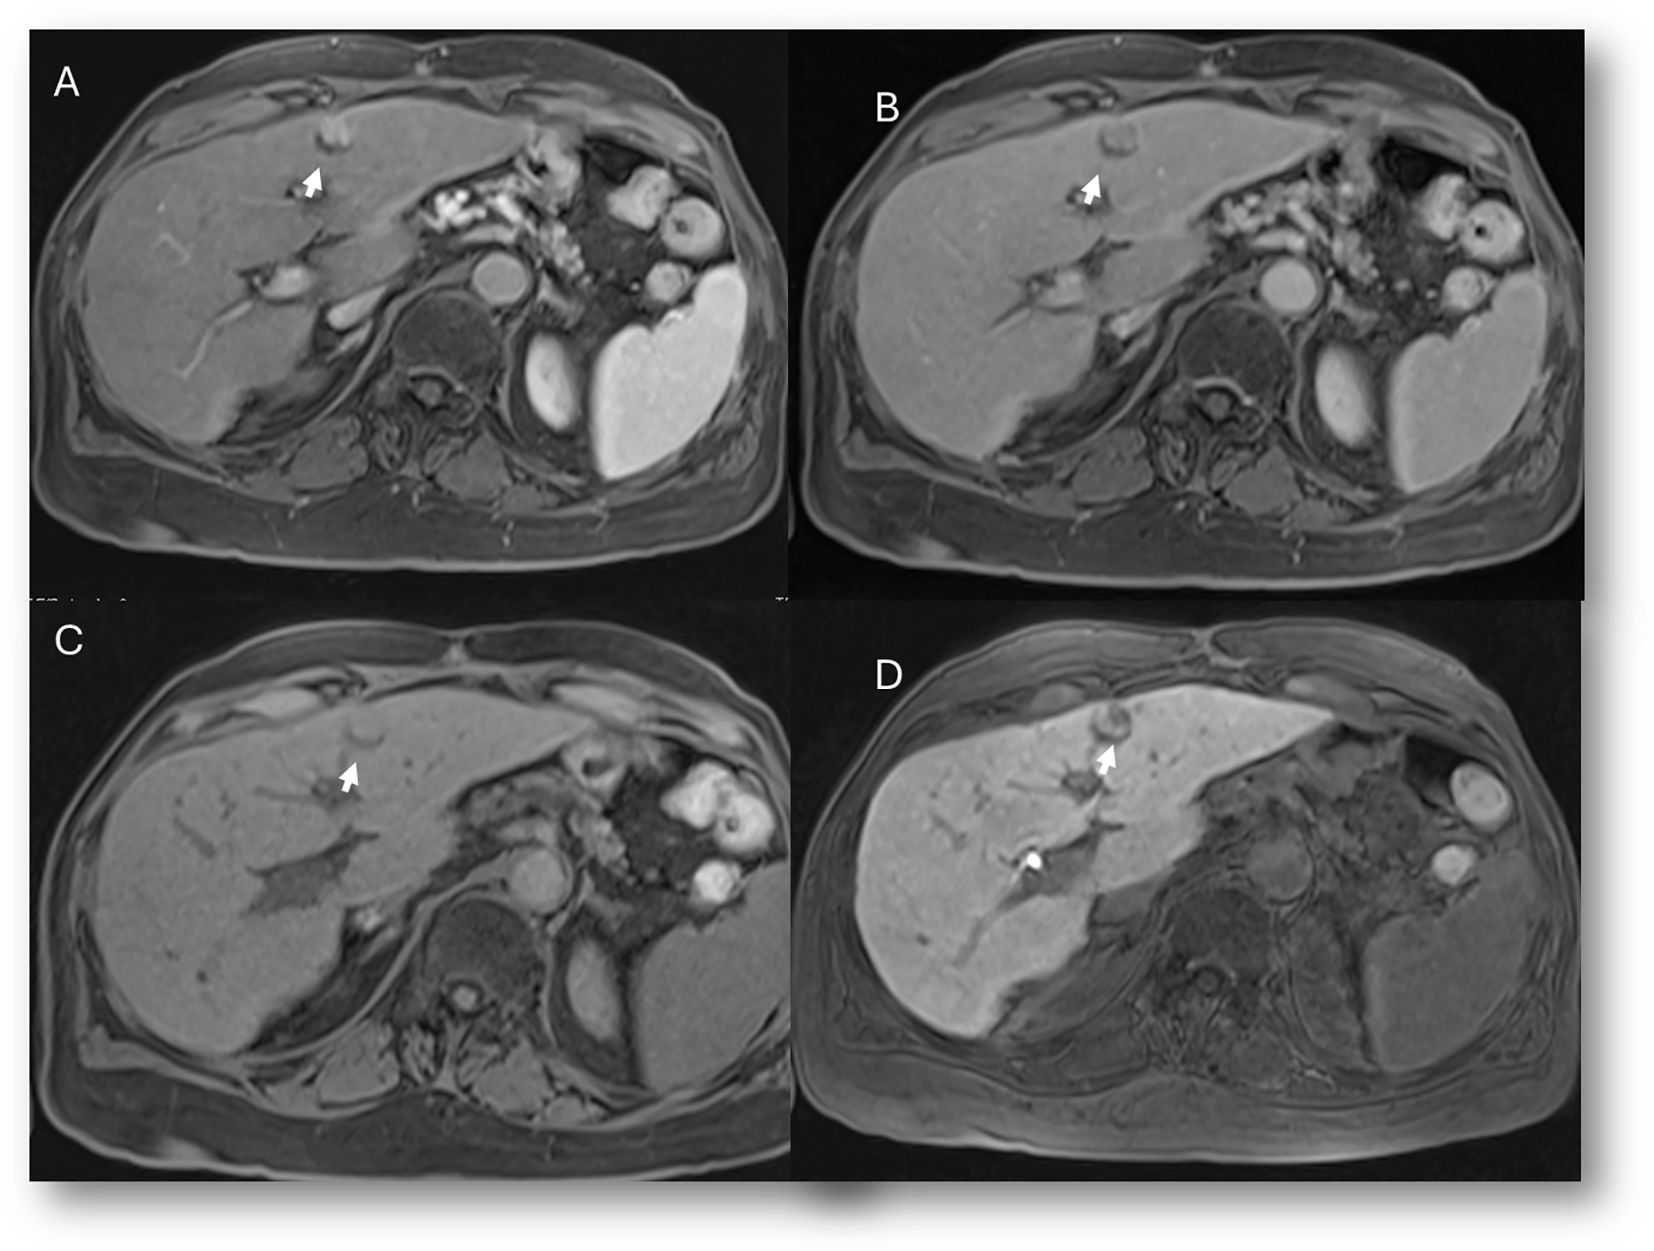

Figure 1. MRI assessment of liver hemangiomas (arrows). In (A) (T2-W sequence, axial plane), the hemangioma (arrow) shows hyperintense signal, and after non-specific contrast agent administration a progressive enhancement is seen (B) T1-W in axial plane during in arterial phase; (C) T1-W in axial plane during portal phase and (D) T1-W in coronal plane during late phase).